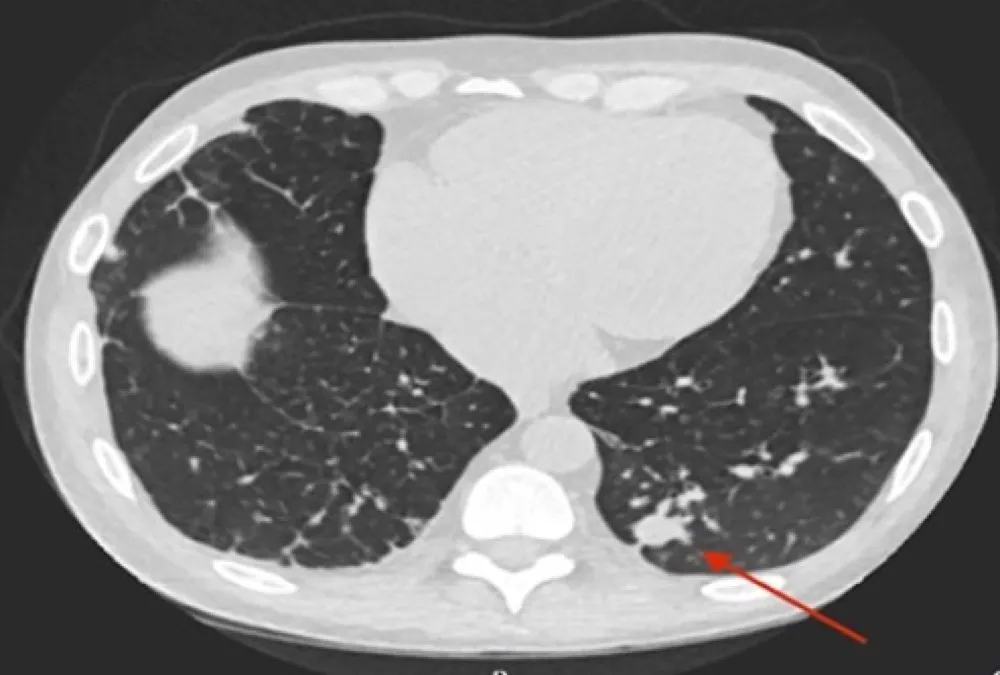

IRA + Icterícia: Um Caso que Exige Investigação Detalhada

IRA + Icterícia: Um Caso que Exige Investigação Detalhada